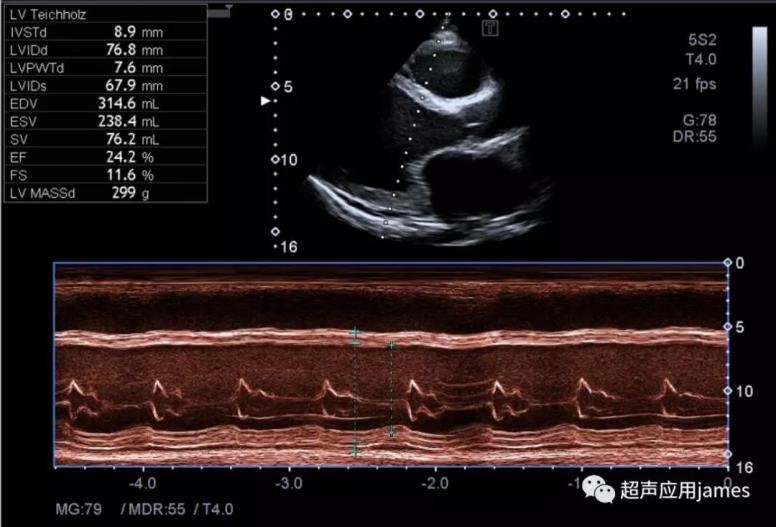

2.超声设备没有配置解剖M型功能,那么心尖上翘患者在左心室长轴切面还有另一种方法就是二维LV-Teich心功能测量方式:

3

采集步骤:获取最佳左室长轴的切面图像,然后冻结图像,启动双副图像,回放图像(左侧回放至舒张末期,右侧回放至收缩末期),打开心功能测量软件包,打开LV-Teich分别测量LVIDd和LVIDs就可得到EF、FS和SV等指标。此步骤的关键同时也是大家容易搞错的地方就是对于时相的选择,舒张末期和收缩末期一定都是二尖瓣和主动脉瓣同时关闭的时候,且保证两个图像在一个心动周期。